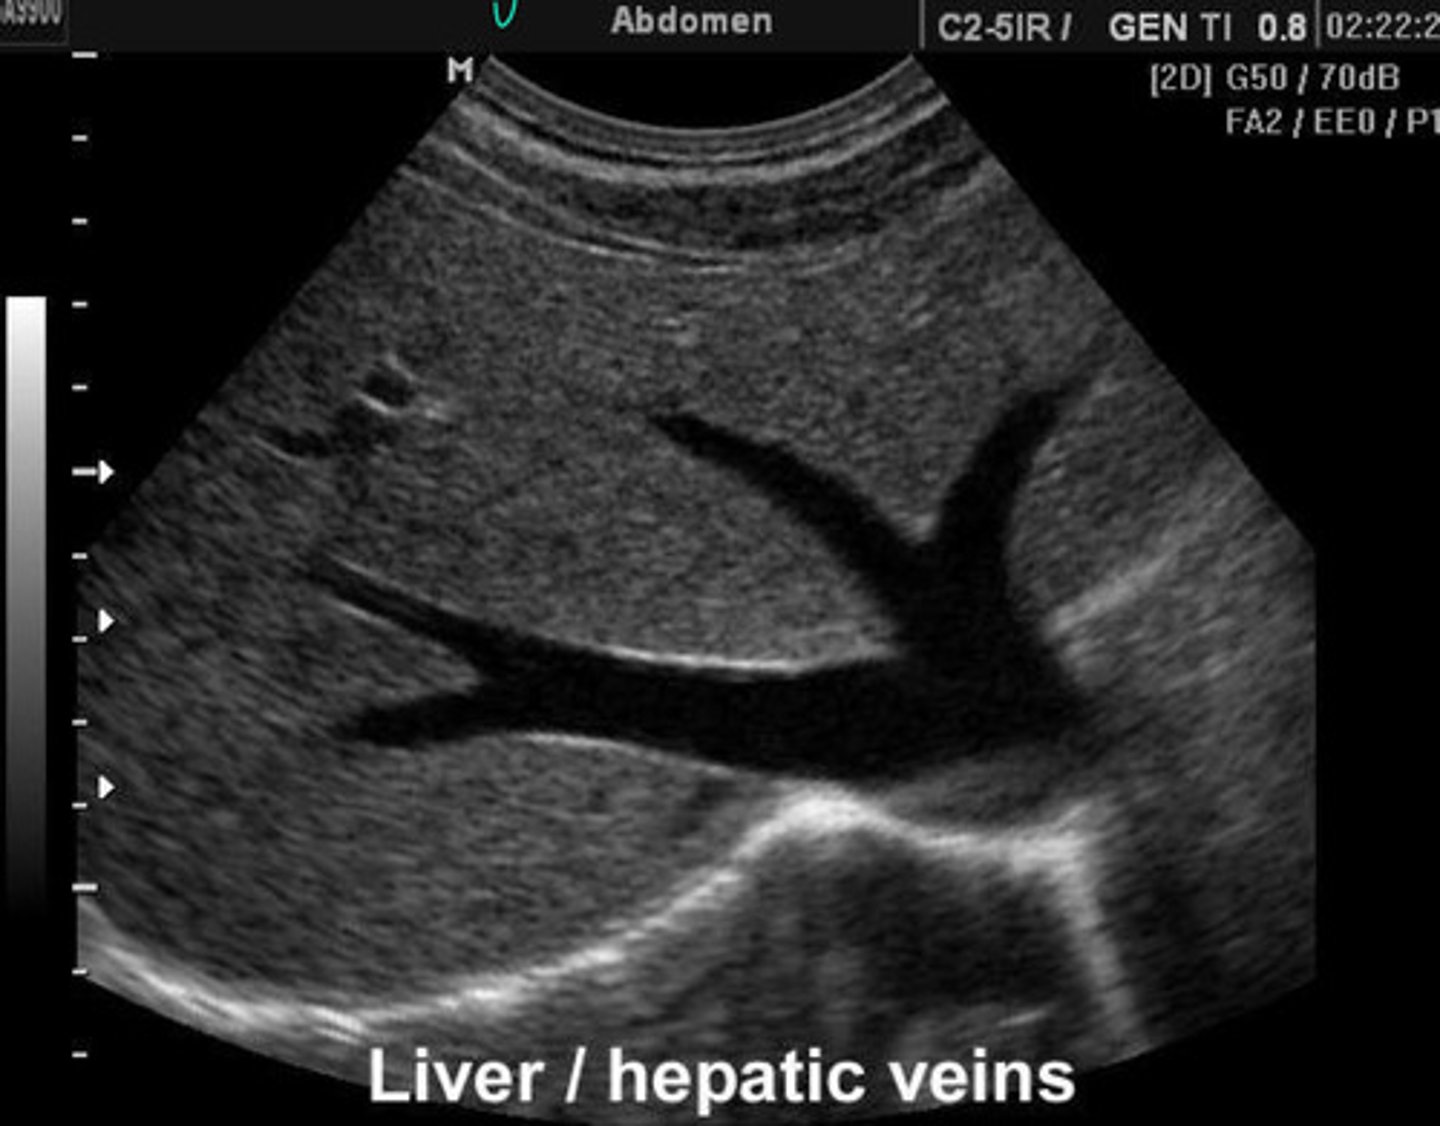

Abnormal = vessels are MASSIVE and congested

What is going on here? Is this normal or abnormal?